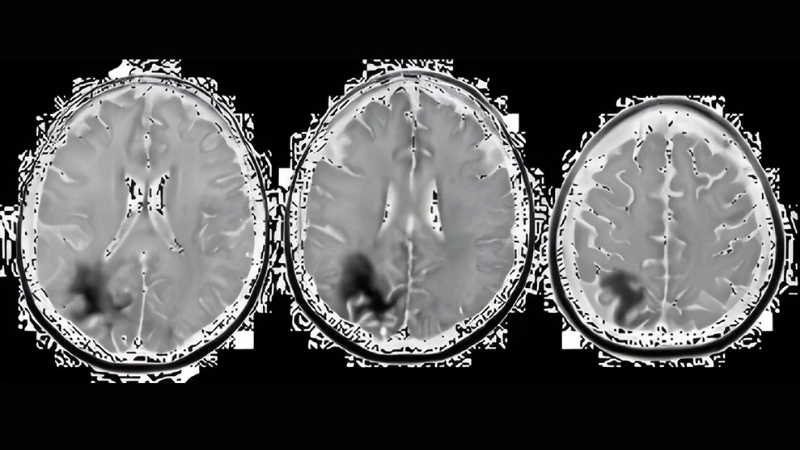

Progressive multifocal leukoencephalopathy cases show severe brain lesions